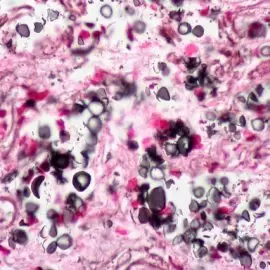

Błonica zaliczana jest do niebezpiecznych chorób zakaźnych wywoływanych przez bakterię – moczugowca błonicy. Bakteria ta wnika do organizmu przez nos lub jamę ustną i kolonizuje błony śluzowe górnych dróg oddechowych. W nielicznych przypadkach może dojść do zajęcia spojówek, ucha środkowego, błon śluzowych narządów płciowych albo zranionej skóry.

Za głównego sprawcę błonicy uznaje się bakterię zwaną maczugowcem błonicy (Corynebacterium diphteriae) produkują silne toksyny. Bakteria może żyć w nosie albo skórze osoby odpornej na chorobę bądź też zacząć rozwijać się w tych miejscach u osoby zarażonej.

Bakteria ta przenosi się drogą kropelkową, podczas kaszlu czy kichania. Jeśli toksyna zostanie wprowadzona do układu krwionośnego, pojawiają się poważne komplikacje zdrowotne.